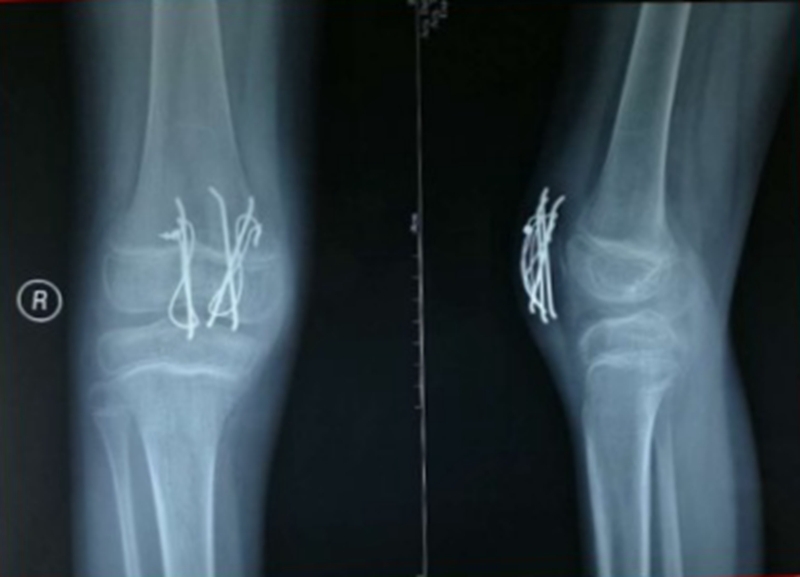

图7 术中X线

图8 术后石膏固定X线